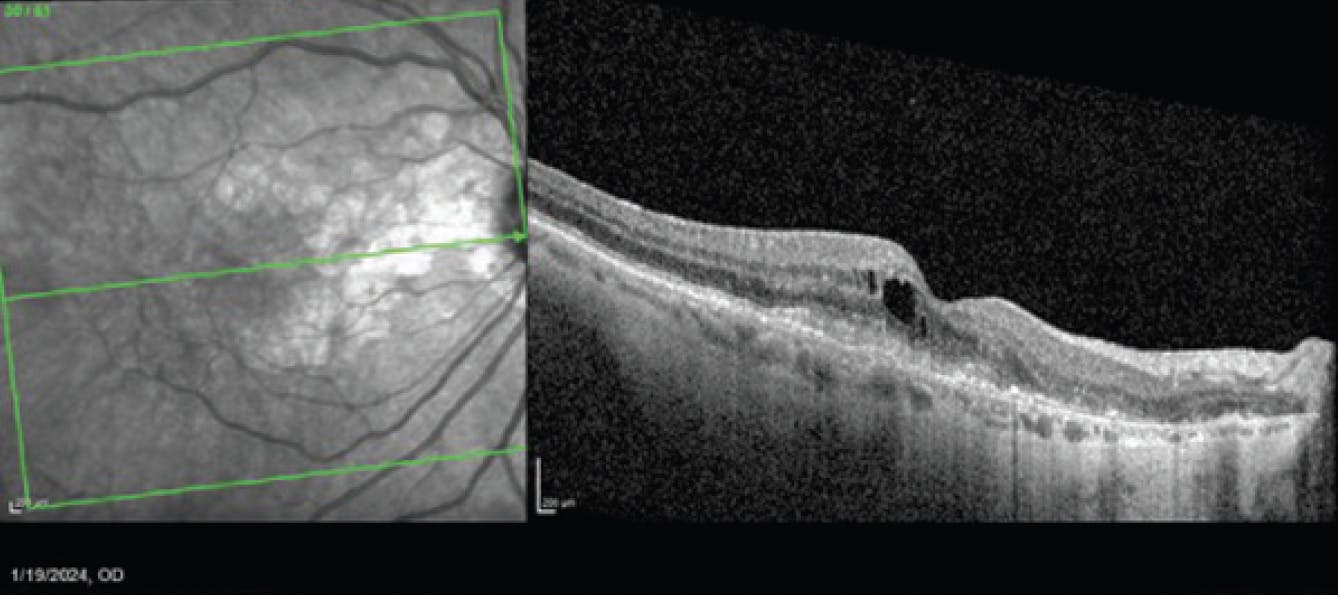

During a January 2024 visit, after 2 monthly injections of avancincaptad pegol, the patient complained of worsening vision OD. On OCT, she was found to have new cystoid macular edema, subretinal fluid, and subretinal hyperreflective material (Figure 4). She was diagnosed with new onset wet AMD and was treated with bevacizumab (Avastin). BCVA at this visit was 20/40. She returned a month later for follow-up, at which time the anatomy had improved, but BCVA was still 20/40 (Figure 5). A second bevacizumab injection was administered.

<p>Figure 5. OCT of the patient in February 2024, 1 month after injection of an anti-VEGF agent to treat the wet AMD.</p>

Figure 5. OCT of the patient in February 2024, 1 month after injection of an anti-VEGF agent to treat the wet AMD.